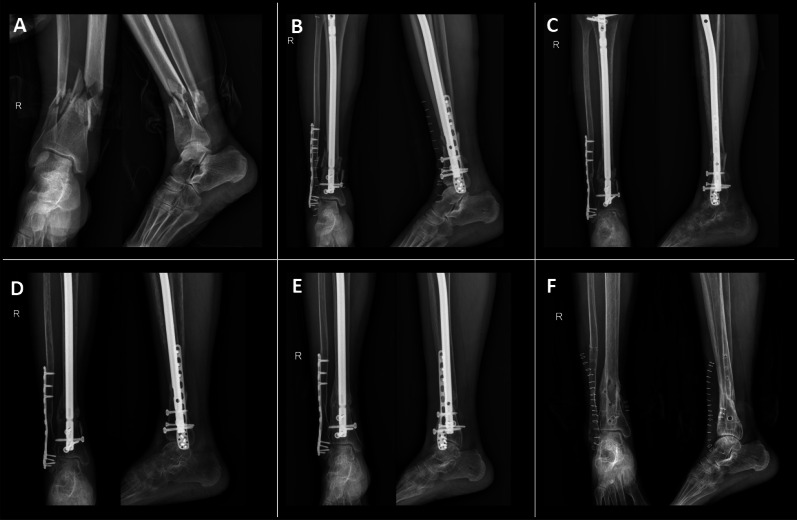

Background: Current literature on ultra-distal tibial fractures (UDTF) is relatively limited, particularly regarding the outcomes and complications of different treatment strategies, with data being notably scarce. This study aimed to compare the clinical outcomes of intramedullary nailing (IMN) and distal tibial plate (DTP) fixation in the treatment of UDTF.

Methods: A total of 48 eligible patients were retrospectively reviewed and divided into two matched groups based on age, gender, injury severity score, and fracture type. The IMN group comprised 21 patients, and the DTP group included 27 patients. All patients were followed up to assess both clinical and radiological outcomes.

Results: The IMN group demonstrated significantly shorter surgery time (P = 0.043) and fracture healing time (P = 0.002) compared with the DTP group. However, no significant differences were found between the two groups in terms of time from fracture to admission (P = 0.740), preoperative hospital stay (P = 0.310), postoperative hospital stay (P = 0.379), infection rates (P = 1.000), or rates of nonunion (P = 0.822). Postoperative malalignment occurred in three patients in the IMN group and one patient in the DTP group (P = 0.430). The mean postoperative angulation in both groups was similar in the coronal plane (P = 0.101) and sagittal plane (P = 0.334). The mean Olerud-Molander Ankle Score (OMAS) was 88.62 ± 5.24 in the IMN group and 85.85 ± 8.39 in the DTP group (P = 0.169).

Conclusion: Both implants are effective in treating UDTF. However, IMN offers advantages in reducing surgical time, accelerating fracture healing, and promoting early recovery. Therefore, IMN may represent a superior surgical option for managing UDTF.